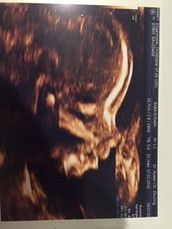

Huhu Tanja klar kann es sein das es geklappt. Aber wenn nicht sei nicht zu sehr enttäuscht. Ich hatte solche Anzeichen auch beim zweiten Kind aber im ersten zyklus war das mehr Wunsch denken. Aber beim zweiten zyklus hatte ich die gleichen Anzeichen wieder und jetzt bin ich in der 23 ssw. Hab damals 3 tage vor tag der periode positiv getestet. Drücke dir die Daumen das es geklappt hat.